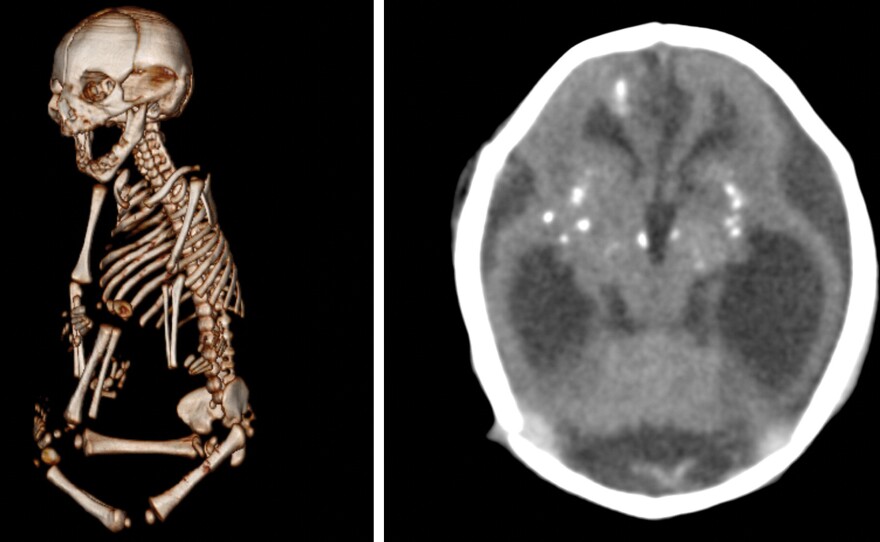

For the study, Levine and colleagues analyzed medical images of 46 fetuses and babies born to mothers who had Zika during pregnancy, including a set of twin girls. The data set included images from 93 ultrasounds, 23 MRI and 41 CT scans taken at the Instituto de Pesquisa in Campina Grande State Paraiba in northeastern Brazil. Doctors also performed autopsies on three babies, who died shortly after birth.

In almost all cases, the babies had damage in the cortex, the outer layer of the brain that controls a huge number of high-level functions like problem-solving, emotion and language. The cortex contains many folds and gives our brains its characteristic shape. But in these babies, oftentimes, the cortex was smooth, Levine says.

All the babies had scars in their brains, called calcifications. These are a telltale sign of an infection, Levine says, and show where the virus has injured the brain — or stopped its development.

The babies also had damage in the brain stem, which controls involuntary actions, like breathing and heartbeat, as well as injuries in the cerebellum, which coordinates muscle activity and voluntary movements.